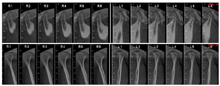

CBCT检查(图4):双侧关节头不对称,开闭口、间隙正常。

牙支持式牵张成骨术[4],即将牵张器固定在牙上,经水平根尖下及牙根间垂直截骨形成牙骨复合体,以连续的牙列作支抗,通过螺杆的旋转牵张力将牙骨复合体送到预定的位置,在牵引力作用下促进新骨的生成,实现骨缺损的修复。常作用于存在大量牙槽骨组织缺损导致植骨难以存活,需要在缺损区形成连续的牙槽骨桥的唇腭裂患者[4,5];也可以用于牙槽裂间隙小,无法通过常规牙槽骨移植修复的患者[6];同时,在缺损的上下颌骨中需要获得充足牙槽骨量及软组织覆盖的病例中,也可选择使用[7]。该方法优点在于保留牙齿,解除拥挤,增加骨量,避免广泛的牙槽骨移植,促进腭咽功能[4];牵张同时产生了新的牙槽骨和牙龈,用于快速正畸牙齿移动[4,8]。有学者[9,10]认为该术式损伤小,有效牵张时间短,患者接受度好,简单高效。由于传统牵张中采用的截骨术创伤大,易发生分离骨段骨坏死,故本病例仅在根尖下行部分骨皮质切开,以期刺激牙周骨质反应。牵张后在短时间内分离出足够间隙(近9 mm),稳定1个月后利用滑动杆的刚性,弹性牵引25。最终通过正颌手术解决患者凹面型,术后建立稳定咬合,治疗效果良好,患者满意度高。X片显示牵张段新骨骨量充足,21、23间裂隙减小,牵张过程中患者无明显不适,未出现牙根吸收、松动,周围牙槽骨段连续(图14)。邻牙牙髓活力测试良好,裂隙周围黏膜可见进一步粘连。最终通过正颌手术解决患者凹面型,术后建立稳定咬合,治疗效果良好,患者满意度高。但由于患者治疗中口腔卫生不佳,导致牙颈部出现明显釉质脱矿,需要多学科的进一步治疗。